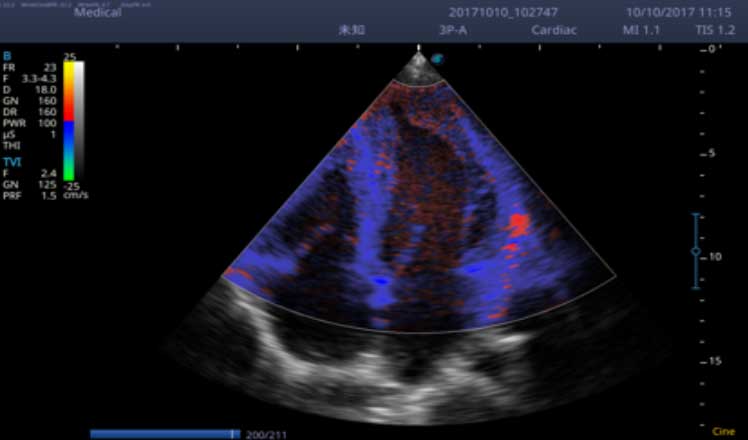

X5采用前端的超声专用芯片,将台式机大规模集成电路完美压缩在笔记本超声的精巧下,提高了系统的运算速度,加载μ-Scan微米成像、脉冲反相谐波等技术,带来优异的临床表现,清晰呈现高分辨率二维图像和层次丰富的血流图像

X5具备实时宽景成像、穿刺增强、彩色M型、组织多普勒等多种高级成像功能,全方位满足多个科室的诊断需求,整机系统向智能化跨越